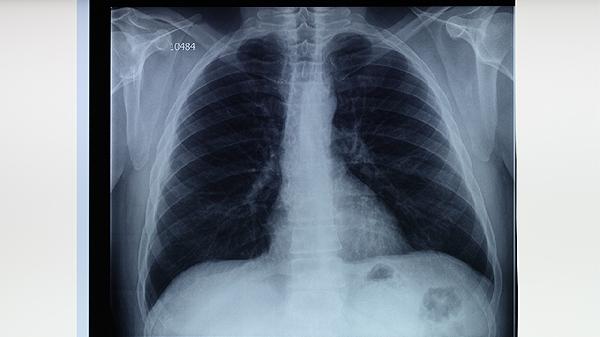

治療肺結(jié)核的化療藥物主要有異煙肼片、利福平膠囊、吡嗪酰胺片、乙胺丁醇片、鏈霉素注射液等。肺結(jié)核是由結(jié)核分枝桿菌感染引起的慢性傳染病,需遵醫(yī)囑聯(lián)合使用抗結(jié)核藥物進(jìn)行規(guī)范治療。

肺結(jié)核患者需嚴(yán)格遵醫(yī)囑完成6-9個(gè)月的規(guī)范治療,不可自行停藥或減量。治療期間應(yīng)保持均衡飲食,適當(dāng)補(bǔ)充優(yōu)質(zhì)蛋白和維生素,避免辛辣刺激性食物。注意隔離防護(hù),咳嗽時(shí)掩住口鼻,痰液需消毒處理。定期復(fù)查胸部影像學(xué)和痰菌檢查,監(jiān)測(cè)藥物不良反應(yīng)。保持規(guī)律作息和適度運(yùn)動(dòng)有助于增強(qiáng)免疫力,促進(jìn)康復(fù)。